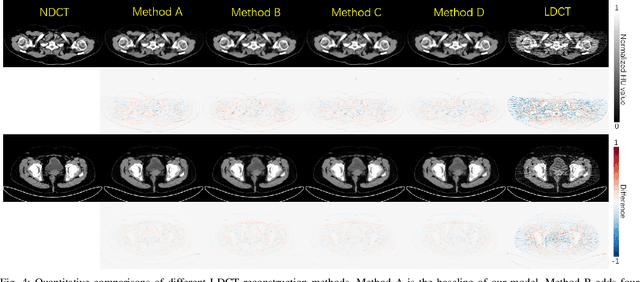

Abstract:Reducing the radiation exposure for patients in Total-body CT scans has attracted extensive attention in the medical imaging community. Given the fact that low radiation dose may result in increased noise and artifacts, which greatly affected the clinical diagnosis. To obtain high-quality Total-body Low-dose CT (LDCT) images, previous deep-learning-based research work has introduced various network architectures. However, most of these methods only adopt Normal-dose CT (NDCT) images as ground truths to guide the training of the denoising network. Such simple restriction leads the model to less effectiveness and makes the reconstructed images suffer from over-smoothing effects. In this paper, we propose a novel intra-task knowledge transfer method that leverages the distilled knowledge from NDCT images to assist the training process on LDCT images. The derived architecture is referred to as the Teacher-Student Consistency Network (TSC-Net), which consists of the teacher network and the student network with identical architecture. Through the supervision between intermediate features, the student network is encouraged to imitate the teacher network and gain abundant texture details. Moreover, to further exploit the information contained in CT scans, a contrastive regularization mechanism (CRM) built upon contrastive learning is introduced.CRM performs to pull the restored CT images closer to the NDCT samples and push far away from the LDCT samples in the latent space. In addition, based on the attention and deformable convolution mechanism, we design a Dynamic Enhancement Module (DEM) to improve the network transformation capability.